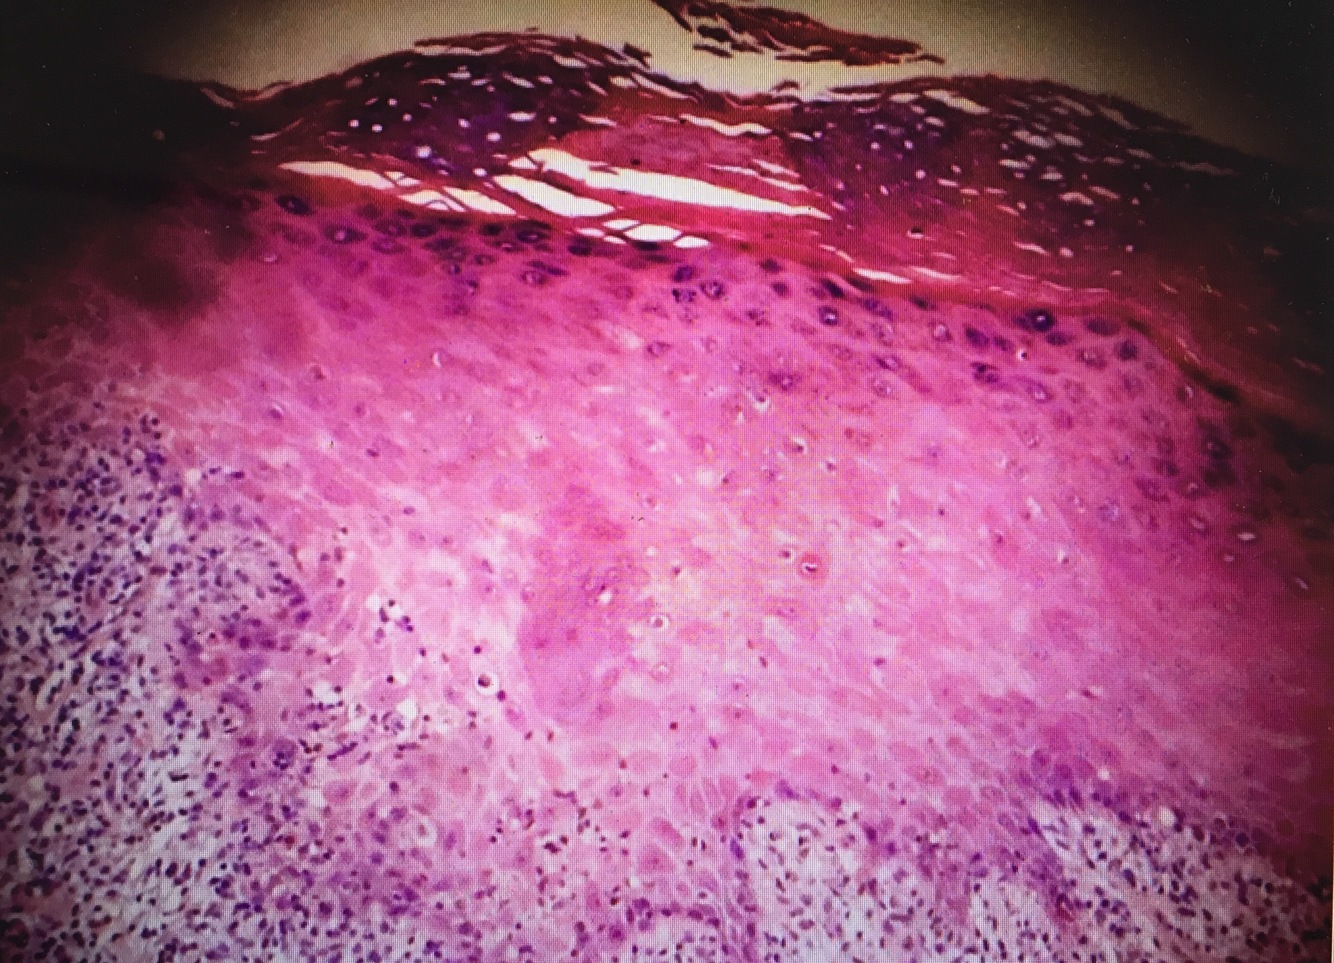

Identify and describe the histology

[Contact Dermatitis Type 4 Hypersensitivity]; [Spongiosis (edema in the intercellular spaes of epidermis)

CD = Weeping, Erythematous, papulovesicular